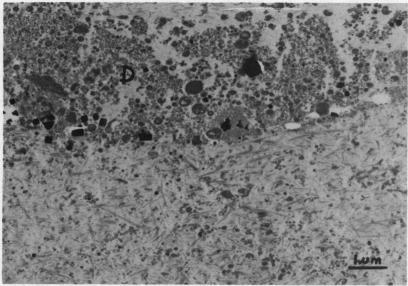

Crystal distribution in articular cartilage of femoral heads resected at hip arthroplasty for fracture of the femoral neck was examined in 10 patients (77-91 years) by computerised image analysis of electron micrographs. Crystal content of the zenith did not differ from that of the infrafoveal region of the femoral head in the superficial 0.5 mm of the cartilage. Crystal area density (percentage area of the section occupied by crystal profiles) was higher in a zone 0-50 microns than in the subjacent zone 50-500 microns from the articular surface, particularly in the zenith of the femoral head. It was also higher on the superficial (towards the articular surface) aspect than on the deep aspect of cells in perilacunar matrix. Crystal area density was similar in lacunar matrix, perilacunar matrix, and matrix remote from cells. Matrix containing cell debris was more heavily impregnated with crystals than any other site. No difference in crystal content was observed in cartilage beneath articular surfaces which were ultrastructurally smooth or roughened. The diminishing gradient of crystal area density with depth from the articular surface, the absence of a marked spatial association with living cells, and the impregnation of sites containing cell debris suggest that crystal deposition in these cases is not due primarily to chondrocyte activity.

通过对电子显微镜照片进行计算机图像分析,对10例(77 - 91岁)因股骨颈骨折行髋关节置换术切除的股骨头关节软骨中的晶体分布进行了检查。在软骨表面0.5毫米处,股骨头顶点的晶体含量与股骨头凹下区域的晶体含量没有差异。晶体面积密度(晶体轮廓所占切片面积的百分比)在距关节表面0 - 50微米的区域高于相邻的50 - 500微米区域,尤其是在股骨头的顶点。在陷窝周围基质中,细胞表面(朝向关节表面)的晶体面积密度也高于深部。陷窝基质、陷窝周围基质和远离细胞的基质中的晶体面积密度相似。含有细胞碎片的基质比其他任何部位都有更多的晶体浸润。在超微结构光滑或粗糙的关节表面下方的软骨中,未观察到晶体含量的差异。晶体面积密度随距关节表面深度的递减梯度、与活细胞无明显空间关联以及含有细胞碎片部位的浸润表明,这些病例中的晶体沉积主要不是由于软骨细胞的活动。